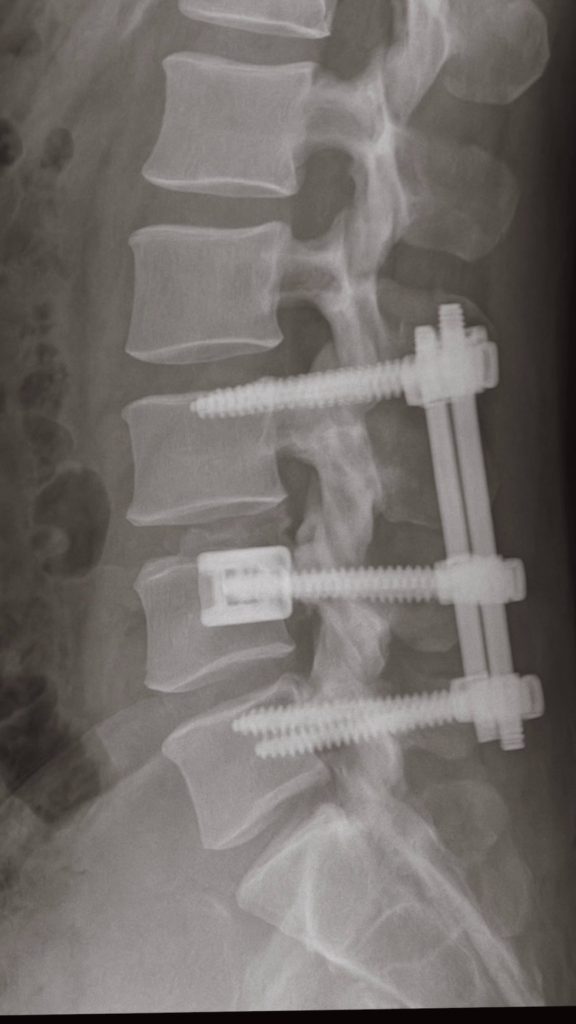

Za poslední měsíce si sáhli na dno. Nikol Moravcová a její manžel Karol Moravec neprožili jednoduché období, které změnilo jejich každodenní život. Náročná operace páteře, dlouhé týdny nejistoty a pomalý návrat zpět – právě to stálo za jejich cestou na Kanárské ostrovy. Místo, kam se Nikol ráda vrací už roky, tentokrát dostalo úplně jiný význam. Nešlo o práci ani odpočinek v klasickém smyslu. Pobyt u oceánu se stal důležitou součástí rekonvalescence. Klid, slunce a mořský vzduch pomáhaly Karolovi postupně znovu získávat sílu po zákroku, který podstoupil před půl rokem.

První týdny po operaci nebyly snadné. Každý krok znamenal opatrnost, každý pohyb kontrolu. Postupně ale přišlo zlepšení. A dnes? Karol se podle všeho cítí natolik dobře, že se vrátil i k aktivitám, které miluje. Dokonce znovu stojí na surfu – symbol toho, že se věci vrací do starých kolejí.